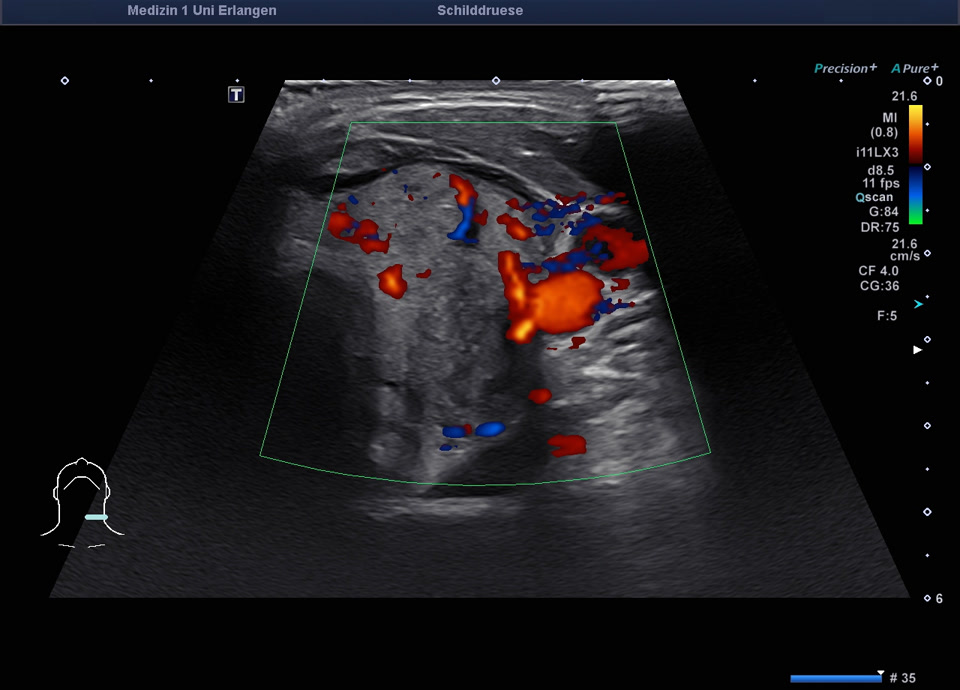

45-year-old male presented patient with persistent sore throat and general symptoms following an EBV-infection. An external diagnosis of post-infectious de Quervain’s thyroiditis had already been made, and a two-week course of corticosteroid therapy was administered. Initial clinical improvement with reduced throat pain was noted under treatment, but symptoms reoccurred after discontinuation of corticosteroids. Laboratory findings revealed leukocytosis of 12,000/µl and CRP of 113 mg/l. Sonographically, a bilaterally enlarged thyroid gland with diffusely hypoechoic areas and inhomogeneous parenchyma was observed. Combined with the patient history, this was characteristic of a subacute thyroiditis with relapse after short-term corticosteroid therapy. Prolonged corticosteroid therapy with slow tapering was performed. Under this regimen, marked clinical improvement occurred within weeks; follow-up ultrasound four months later showed a normal-sized thyroid with only mildly inhomogeneous parenchyma, consistent with resolving thyroiditis.